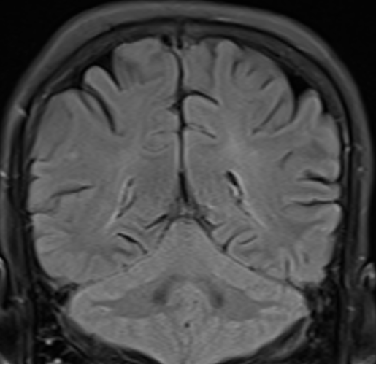

2013-8-2 MRI

2013-8-2 CT

腰穿脑压240